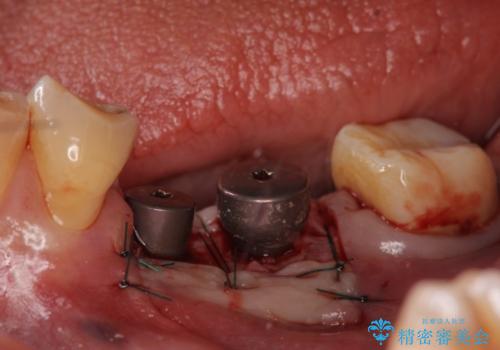

欠損部位である左下5、6番目にインプラントを埋入し、オールセラミッククラウンによる補綴を行いました。

ストローマンについて

当院では主にストローマンという種類のインプラントを治療に用いています。

ストローマンは世界的にもNo1のシェアを誇り、骨との適合にも優れたインプラントです。

カスタムアバットメントについて

カスタムアバットメントは患者様それぞれの歯茎に合わせて製作されたオーダーメイドのアバットメントです。

既製のアバットメントに比べ適合がよく、高い清掃性を誇ります。